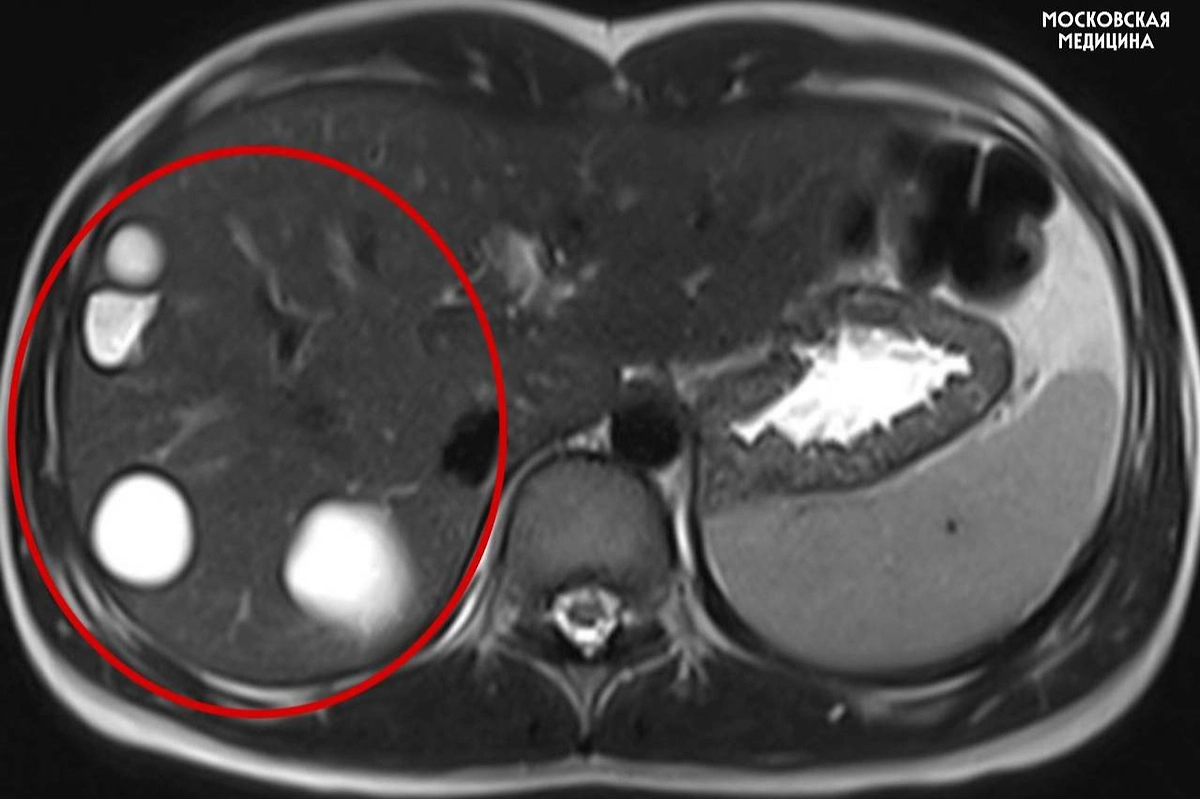

В столичной больнице имени Сперанского врачи спасли 14-летнюю девочку, у которой случайно обнаружили сразу несколько паразитарных кист печени. Находку сделали во время обычного планового обследования — никаких ярко выраженных симптомов у ребёнка не было. После диагностики школьницу сразу направили на операцию. Об этом в московском департаменте здравоохранения.

Как рассказал заведующий хирургическим отделением профессор Игорь Хворостов, эхинококкоз чаще всего выявляется поздно, так как его признаки — боль, лёгкая температура, тяжесть в животе или аллергия — выглядят неспецифичными. Хирурги провели лапароскопическую операцию и удалили пять кист. Уже через пять дней после вмешательства пациентку выписали домой.